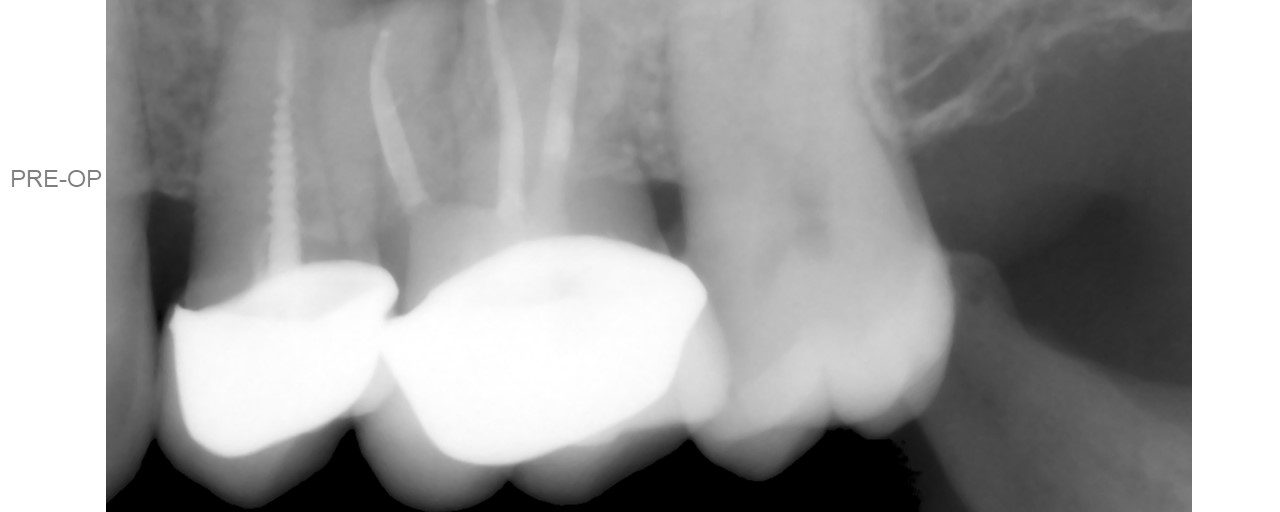

Apexogenesis + Selective Endo

Patient was to be reviewed 2 weeks after initial treatment. Turned up after 3 years. The distal canal had a Nice layer of Dentin. I left it alone. Should I have gone in?